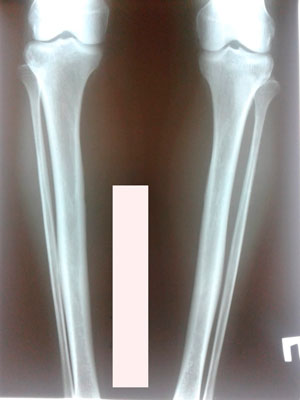

Исходник - 50 лет.

Дата операции - 30.07.2019г.

IMG_4666-29-07-19-10-13.JPG

IMG_4671-29-07-19-10-13.JPG